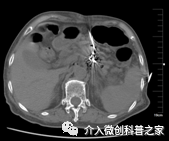

中晚期胰腺癌侵及十二指肠行十二指肠支架植入治疗

(解除肠道梗阻保持通畅)